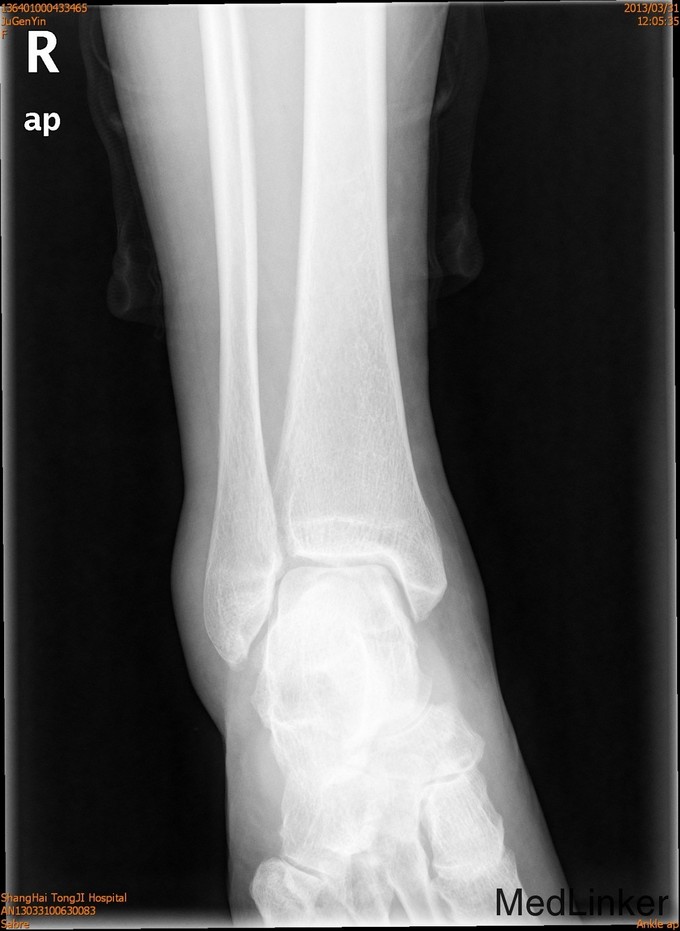

患者女,61岁,摔伤后右踝足肿痛4天。患者4天前不慎摔伤,即感右足踝疼痛,肿胀,活动受限 ,休息后疼痛减轻,X线示右外踝骨折。

查体:一般情况可,右外踝肿胀,淤青,压痛明显,可及骨擦感,足部活动感觉可。

诊断为右外踝骨折,完善术前检查后于全麻下行右外踝骨折ORIF术+距腓前韧带修复术。